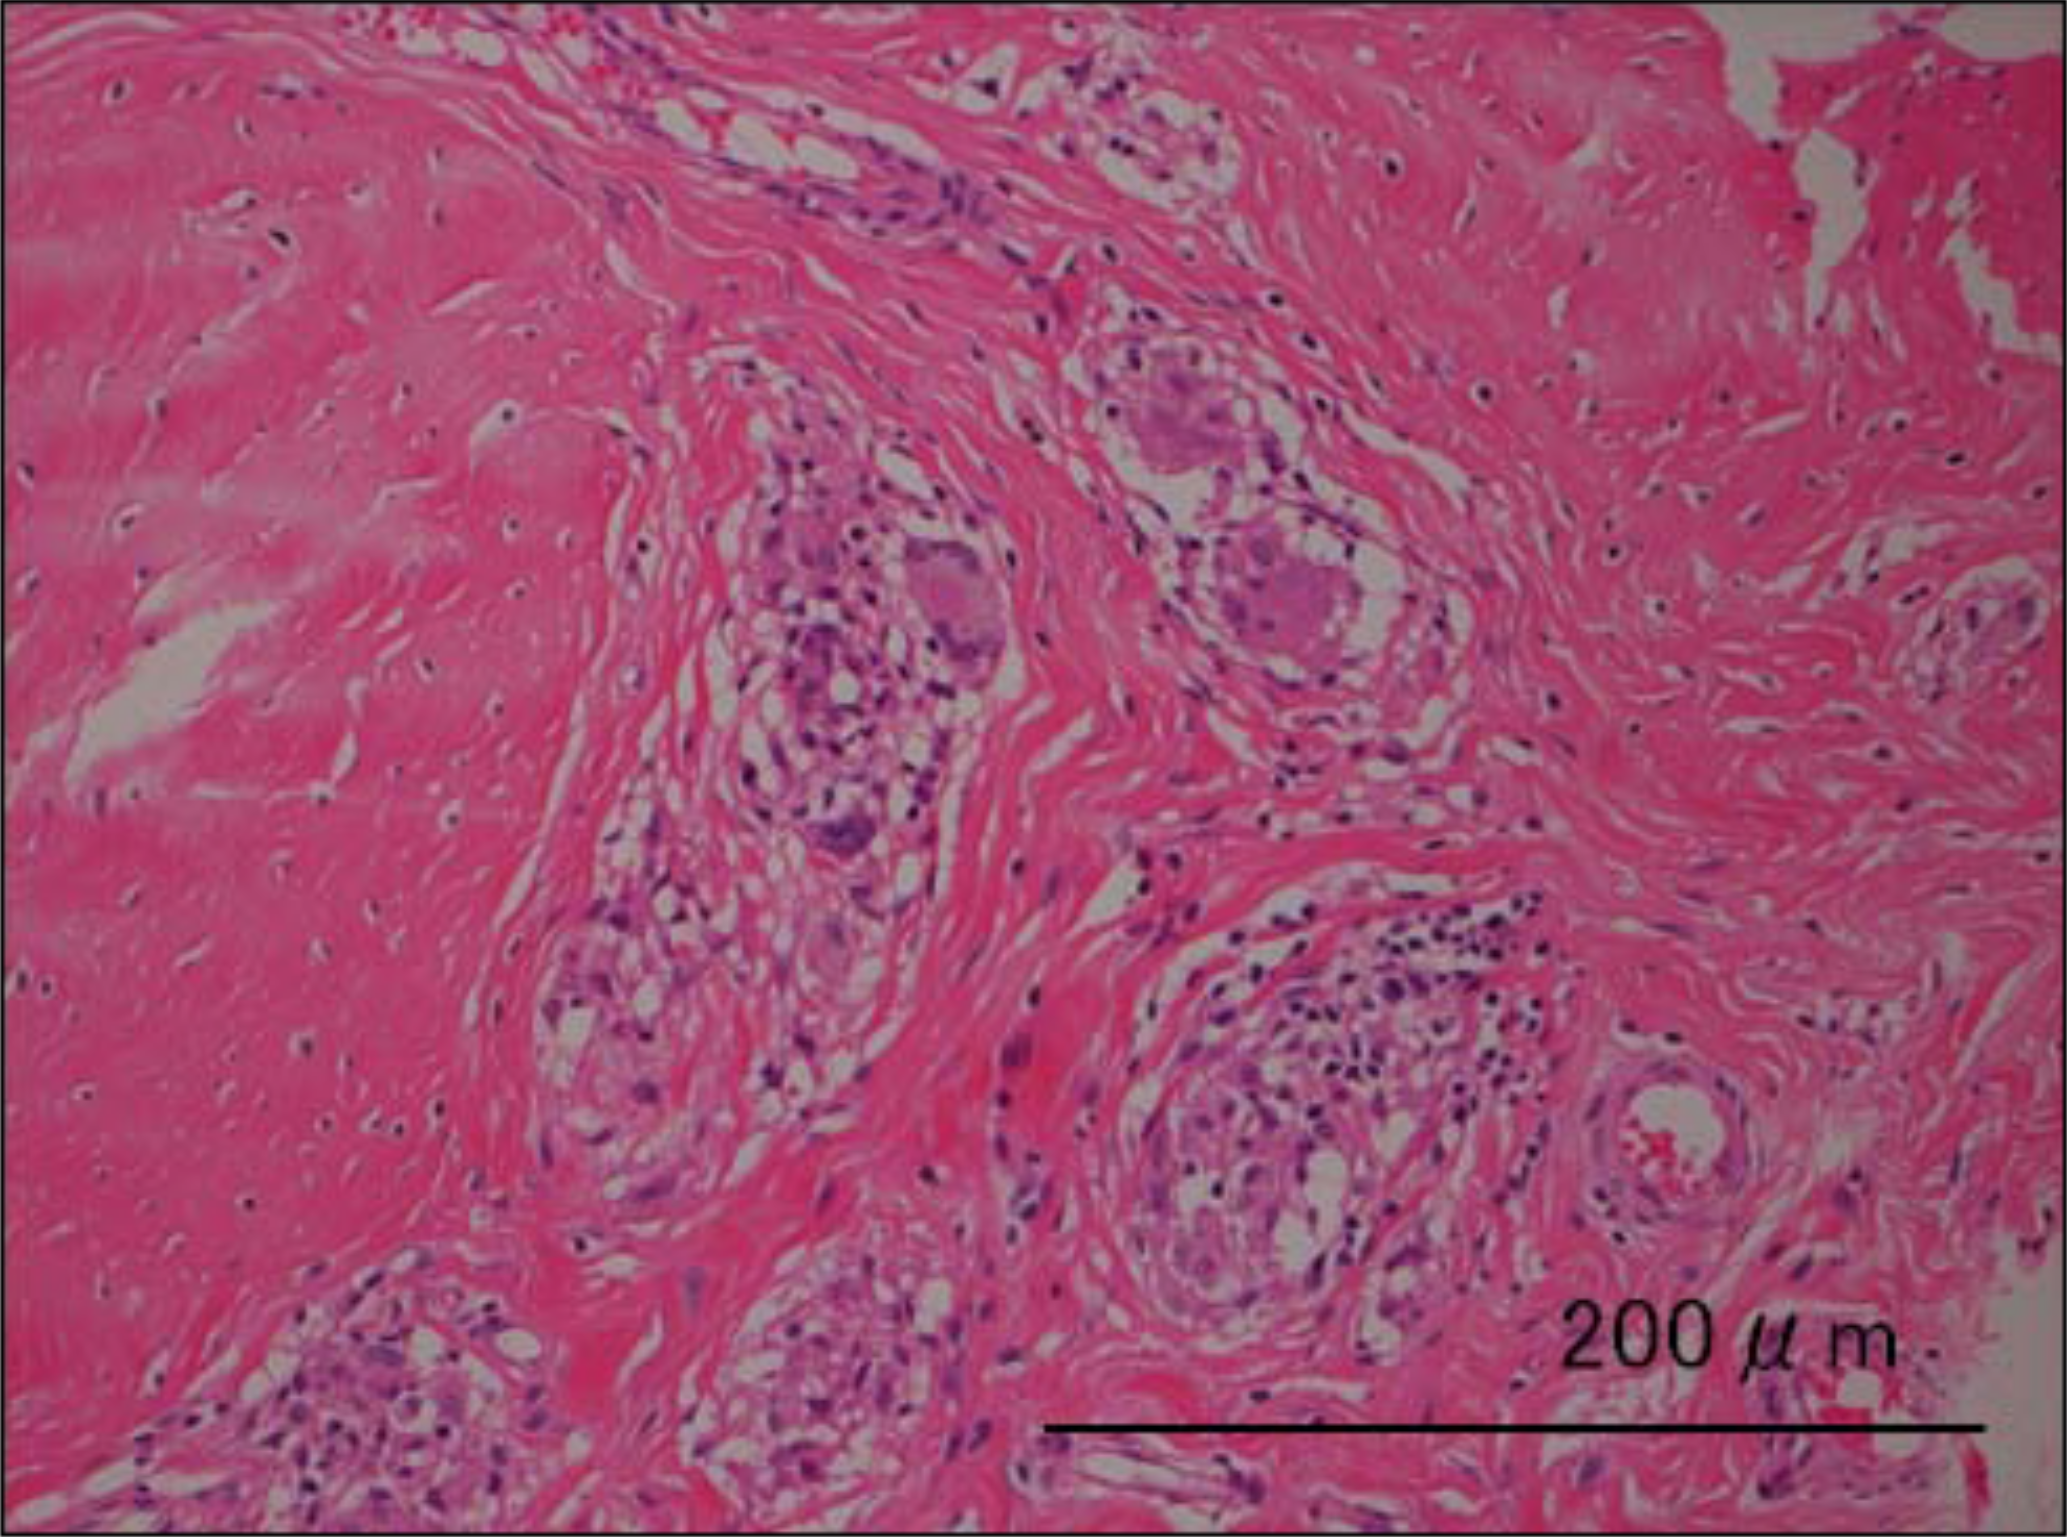

Metal concentrations of the joint fluid were Co 640 ng/ml and Cr 100 ng/ml. Intraoperative cultures were negative. Hypertrophy of the synovial tissue and a huge pseudocapsule were noted and completely resected. The femoral head-neck junction demonstrated obvious corrosion (Figure 4). The modular neck and femoral components were wellfixed. The 40-mm metal head, neck, and stem were replaced with a 32-mm delta ceramic head BIOLOX® (CeramTec AG, Plochingen, Germany) and Profemur R® stem (Ti, 6Al, 4V). Histological examination showed peri vascular lymphocyte infiltration, necrotic tissue, and giant cells (Figure 5).

Figure 5: Pathological specimen in Case 1 (hematoxylin and eosin, ×20). See text.

The modular neck and femoral components were well-fixed. The implants were replaced with a 36-mm delta ceramic head (BIOLOX®) and Profemur-R® stem with a modular neck. Metal concentrations of the joint fluid were cobalt 3 ng/ml and chromium 32 ng/ml. Pathology was similar to that of Case 1 (Figure 9).

ARMD was reported in late 2000 in MoM hip resurfacing [1,26]. Pseudotumors were also reported in late 2000 with the same systems [8]. These reactions were investigated as hypersensitivity to metals [6]. Histomorphological study showed an aseptic lymphocytic-dominant vasculitis-associated lesion (ALVAL), as shown in Figure (5) and Figure (10).

Figure 10: Pathological specimen of Case 2 (hematoxylin and eosin, ×20). See text.